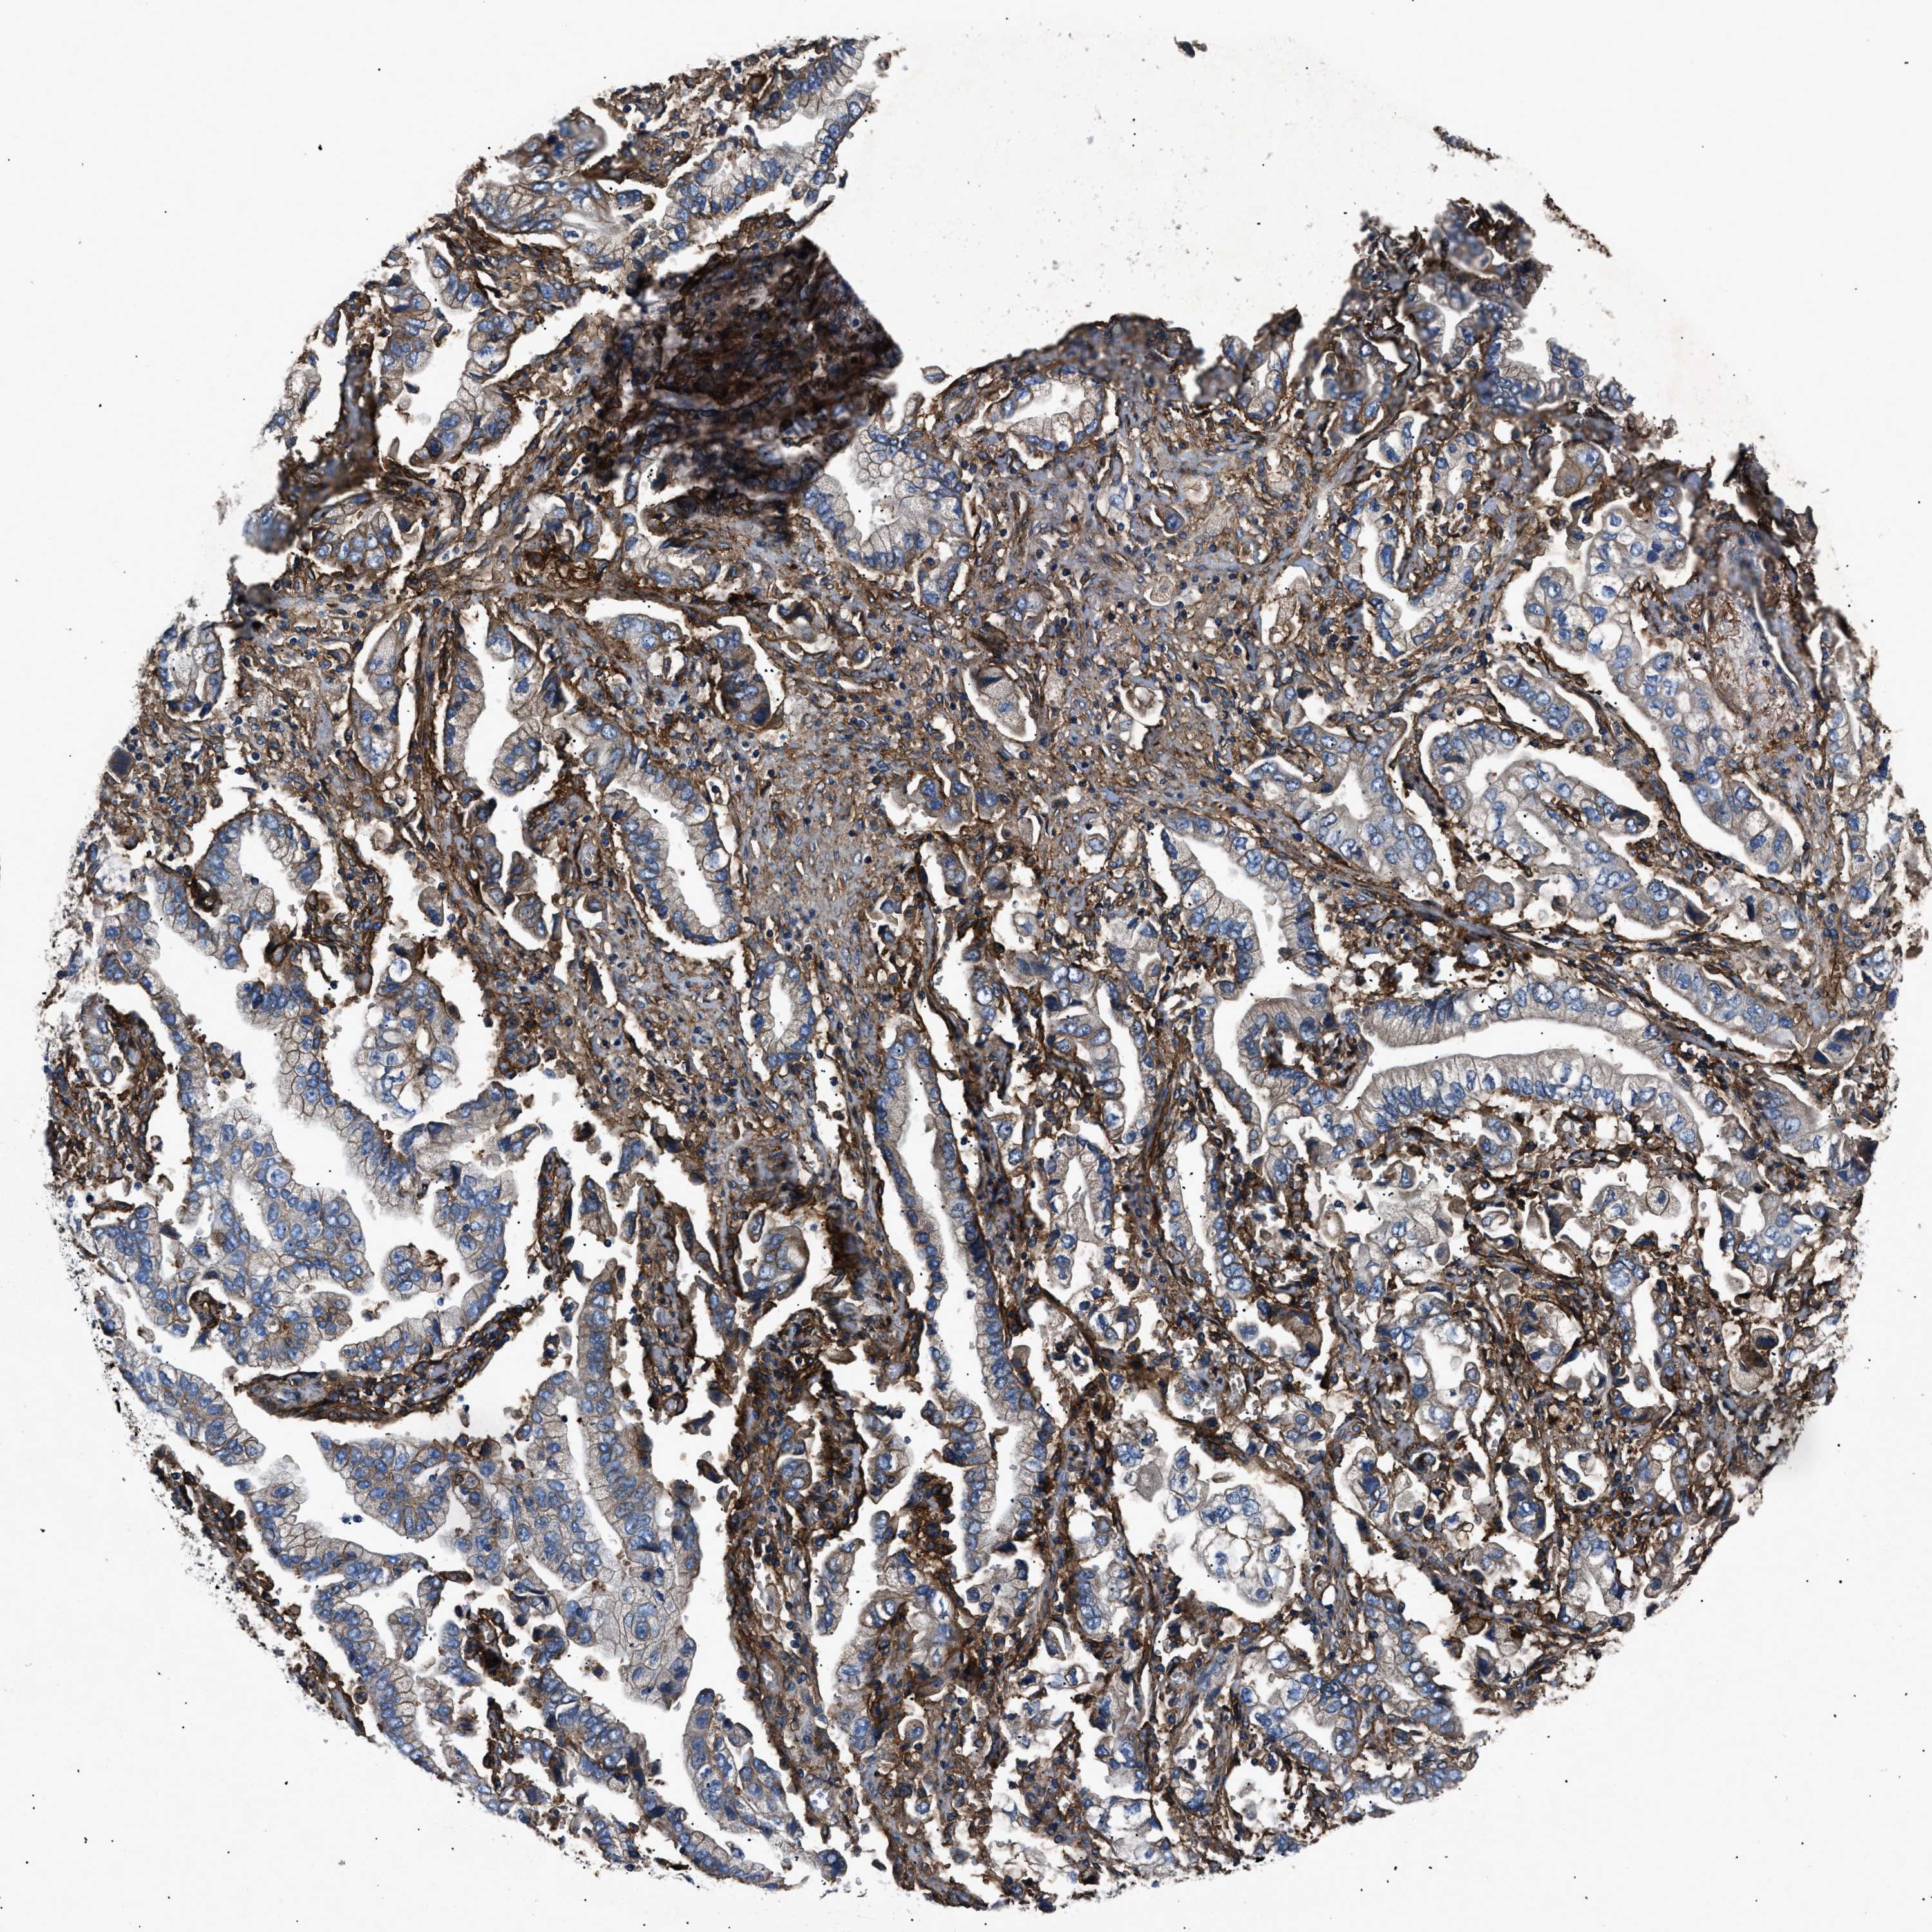

STOMACH CANCER - Protein expressioni

A mouse-over function shows sample information and annotation data. Click on an image to view it in a full screen mode. Samples can be filtered based on level of antibody staining by selecting one or several of the following categories: high, medium, low and not detected. The assay and annotation is described here.

Antibody stainingi

Antibody staining in the annotated cell types in the current human tissue is reported as not detected, low, medium, or high, based on conventional immunohistochemistry profiling in selected tissues. This score is based on the combination of the staining intensity and fraction of stained cells.

Each image is clickable and will lead to virtual microscopy that enables deeper exploration of all samples and also displays staining intensity scores, fraction scores and subcellular localization as well as patient and tissue information for each sample.

Antibody HPA009285

Antibody HPA017139

Antibody CAB017826

Staining

High

Medium

Low

Not detected

Intensity

Strong

Moderate

Weak

Negative

Quantity

>75%

75%-25%

<25%

None

Location

Nuclear

Cytoplasmic/membranous

Cytoplasmic/membranous,nuclear

Adenocarcinoma, NOS

Adenocarcinoma, High grade